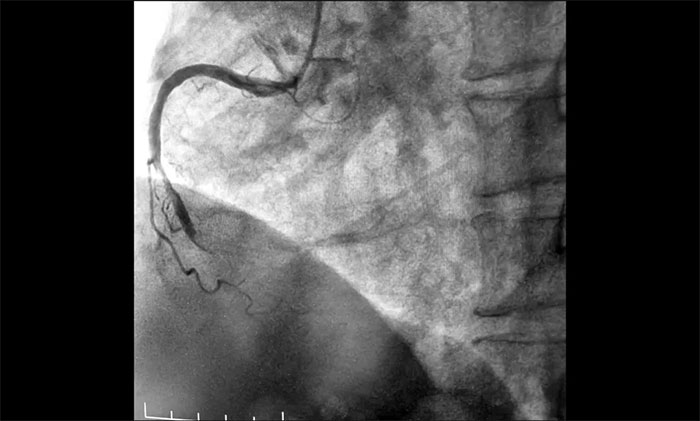

近日,上海藍(lán)十字腦科醫(yī)院為一名急性心;颊邔(shí)施介入手術(shù)。該患者因“間斷心前區(qū)不適伴咽部束縛感7小時(shí),全身乏力3小時(shí)”入院,綜合其病史和相關(guān)檢查確診其為急性下壁心肌梗死,隨時(shí)有猝死風(fēng)險(xiǎn),手術(shù)指征明確。經(jīng)球囊擴(kuò)張和支架置入,開通閉塞血管,助其恢復(fù)心肌供血。

▲ 術(shù)前,前降支、回旋支、右冠狀動(dòng)脈嚴(yán)重狹窄及完全閉塞